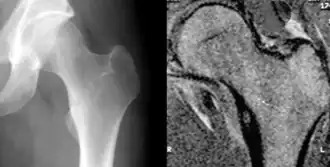

Остео́ид-остео́ма - остеоидная остеома, доброкачественная медленно развивающая опухоль составляет 9-10% среди всех доброкачественных опухолей костей. У мужчин встречается в 4 раза чаще, чем у женщин, болеют преимущественно люди молодого возраста (от 10 до 20 лет).

Клиника и диагностика

Клиника: Ведущим симптомом является боль, особенно выраженная по ночам. При губчатых остеоид-остеомах интенсивность болевого синдрома менее выражена, чем при кортикальных В случае поражения эпифизов могут возникать суставные боли. Иногда определяются припухлость и болезненность при давлении. Со стороны периферической крови отклонений от нормы нет.